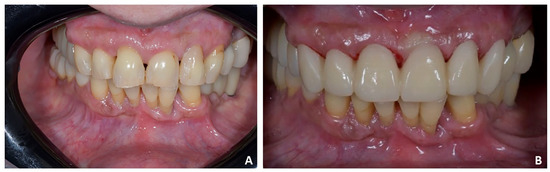

Orthodontic set-up. The orthodontic treatment aimed to optimize the position of the anterior teeth for the final prosthetic rehabilitation. In particular, the treatment plan involved the reduction of incisors flaring and diastemas to correct incisal guidance and better support prosthetic crowns and smile aesthetics. The programmed orthodontic movement was staged, and eight aligners were required to achieve the final pre-prosthetic teeth position. The patient wore each aligner for two weeks for a total treatment time of 4 months (Figure 18A,B).

Figure 18. Case 3. (A) Orthodontic set-up (Invisalign Go platform); (B) intra-oral photograph with clear aligner.